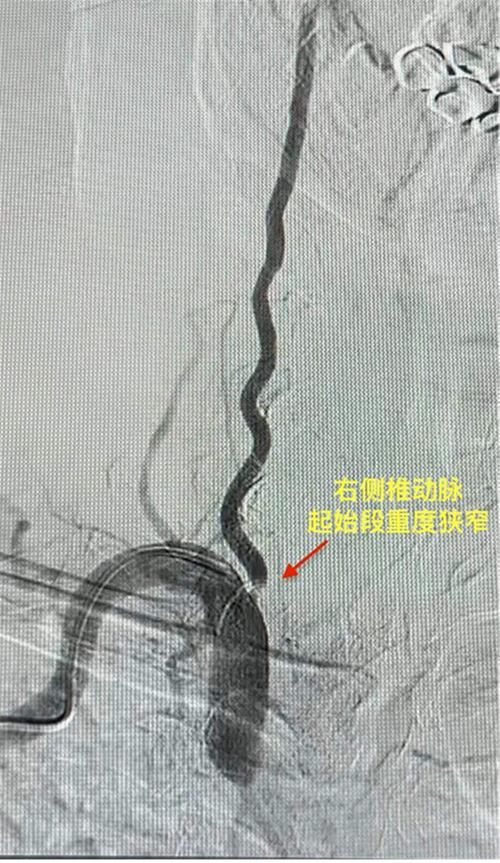

△ 術(shù)前右側(cè)椎動(dòng)脈起始段重度狹窄

1月26日,尹大爺因“頭暈、聲嘶,伴有步態(tài)不穩(wěn)及飲水嗆咳2天”到市中區(qū)人民醫(yī)院就診,考慮為,急性腦干梗死。醫(yī)院立即啟動(dòng)卒中綠色通道,急診行頭顱MRI+DWI+MRA提示,急性腦干梗死(延髓左份)。其間,考慮到尹大爺高齡和患有高血壓等基礎(chǔ)疾病,醫(yī)院立即組織開(kāi)展MDT討論,制定了詳細(xì)的血管內(nèi)治療手術(shù)方案,征得患者及家屬同意后,神經(jīng)內(nèi)科團(tuán)隊(duì)在局麻下進(jìn)行右側(cè)椎動(dòng)脈支架植入術(shù),手術(shù)順利,術(shù)后復(fù)查頭頸部CTA提示右側(cè)椎動(dòng)脈起始部狹窄解除。